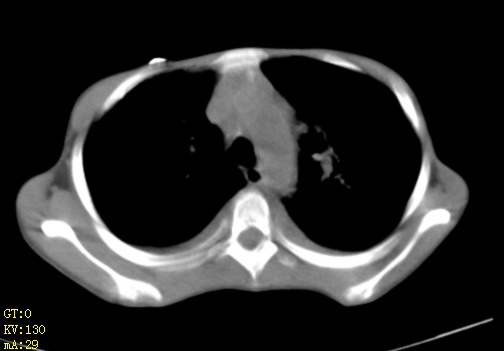

女,12岁,气促、咳嗽2天,3个月前查胸片示:两肺感染,急诊入院查ct,血常规等未检查。

左肺上叶改变考虑继发性肺结核,余双肺重症肺炎不排除h1n1。双侧胸腔少量积液。

双肺中下野不规则片絮状阴影,中外带明显,双侧胸腔少量积液,心影增大,心腔密度减低,隆突下及左侧气管旁见钙化淋巴结影,考虑双肺感染、心衰;建议结合临床除外h1n1并急性心衰,先心不能排除。

两肺多发片絮状模糊影,以下肺外带居多,内见支气管气像,纵膈窗未减影,两侧胸腔积液,心影增大,结合心超,支持重症肺炎,非常时期,甲型h1n1流感不排除。